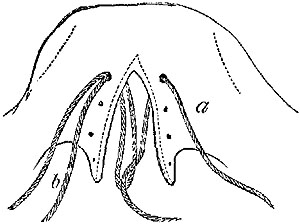

2. Ligature of Lingual.—To secure this vessel either before it becomes concealed by the hyo-glossus, or after it is under the muscle, a curved incision is necessary, following the line of the hyoid bone, and especially of its greater cornu, but a line or two above its upper border. After the skin and platysma are divided, the posterior belly of the digastric must be{33} recognised, which again will guide to the posterior edge of the hyo-glossus. The edge of the sub-maxillary gland may very probably require to be raised out of the way. The artery can then be secured, either before it dips under the hyo-glossus muscle, or after it has done so, by the division of a few of its fibres on a director. Care is needed to avoid injury of the hypo-glossal nerve, which lies above the muscle.